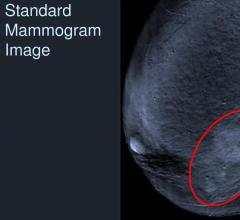

Researchers have found that digital breast tomosynthesis (DBT) led to reduced recall rates and an increase in cancer detection in a large breast cancer screening program.

Despite decades of progress in breast imaging, one challenge continues to test even the most skilled radiologists ...